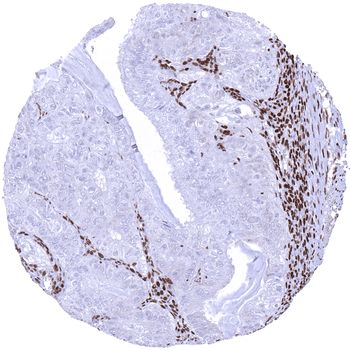

Ovary Malignant Mixed Mullerian tumor with strong MSH2 positivity in stromal and inflammatory cells but absence of staining in tumor cells.